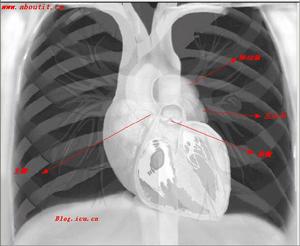

血管造影顯示:管腔不規則,管腔狹窄與閉塞,管腔呈瘤樣擴張。心血管疾病的超聲診斷外,影像學中亦能發現血管壁增厚,管腔狹窄等病變。影像學中X線體層檢查亦能發現血管壁增厚,管腔狹窄等病變。影像學中磁共振檢查亦能發現血管壁增厚,管腔狹窄等病變。